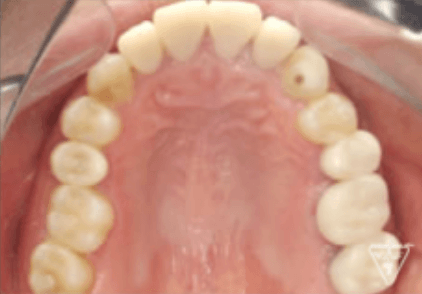

治療後